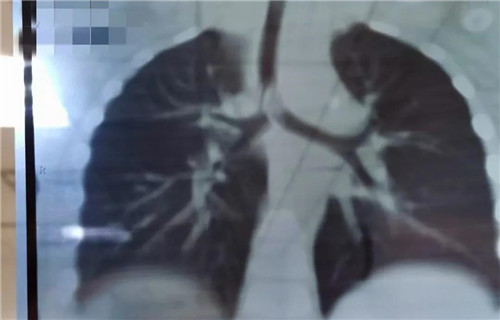

22日晚,19个月女宝诺诺(化名)在家吃花生突然呛咳,爸爸把她倒过来拍几下,诺诺吐出半个花生,但没好转,又出现喘憋,情况非常紧急......夫妻俩立即带孩子来到德州扑克游戏网 就诊,耳鼻喉科夜班医生接诊。医生初步判断是气管异物,而且很可能在主气道。肺CT三维重建显示,异物正堵在主支气管与分叉气管交接口,基本堵满了,诺诺出现吸气性呼吸困难。情况紧急,考虑急诊手术取出。当晚9点多,诺诺住院。此时,耳鼻喉科主任沙颖、副主任李莉萍、刚加完班回家的李萍大夫,麻醉科主任王丽波也正在从家往医院赶。

当晚12点,诺诺进入手术室。因为异物占据气道,孩子又小,取异物一定要快。支气管镜进入后显示,半个完整花生堵在主支气管分叉位置,堵塞面积达到4/5以上,仅在花生边缘与气管之间留有少许通气的地方。花生已经被浸泡得很软了,异物钳夹过程中,不能完整夹持,抓出来的都是或大或小的碎块。随着一块一块碎花生被取出,诺诺的呼吸渐渐地好了起来。诺诺被推回病房时,已经快凌晨2点了。